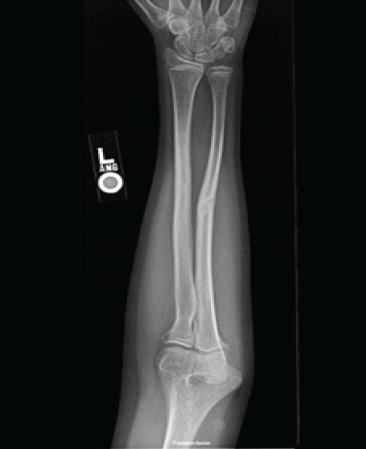

Radiographic evaluation of the left forearm showed a healed both-bone forearm fracture with good alignment (Fig. 2 and 3).

Figure 3: Anterior-posterior X-ray demonstrating well healing both bone fractures.